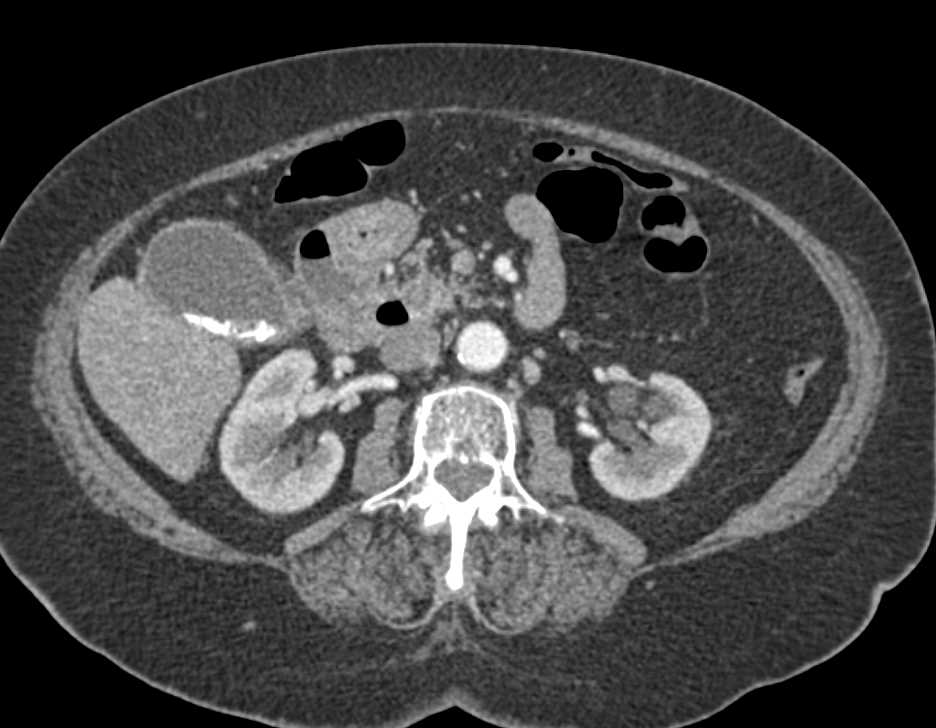

Partially Calcified Common Bile Duct (CBD) Stone in Distal Duct